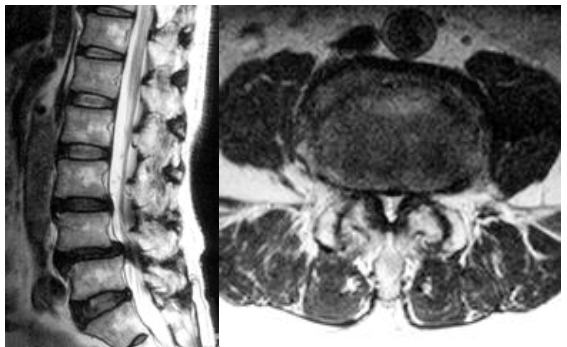

MRIを確認すると第4腰椎と第5腰椎間での馬尾神経の圧迫が明瞭です。